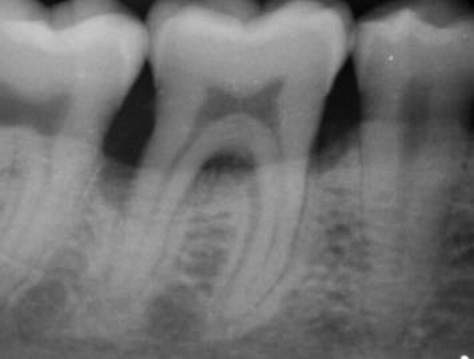

I mange tilfælde kan paradentose behandles med ikke-kirurgiske metoder, såsom ved at der opretholdes optimal mundhygiene og udføres tandrensning, hvor tændernes rødder også renses (tandrodsrens). Men når sygdommen er fremskreden med betydelig skade på tandkød og knoglevæv, kan kirurgisk behandling være nødvendig. Tandlægen vil typisk anbefale kirurgi, når der er vedvarende betændelse. Det gælder, når der er:

• dybe tandkødslommer, som forhindrer effektiv renholdelse.

• knogletab, som kræver genopbygning.

Operationen udføres for at reducere dybe tandkødslommer, hvor bakterier kan samle sig. Tandlægen lægger tandkødet til side for at fjerne plak og tandsten fra rødderne, hvorefter tandkødet sys tættere til tanden for at mindske lommens dybde og gøre det nemmere at holde området rent fremover.

Vævsregenerering og knogletransplantation

Denne teknik bruges til at stimulere genvækst af patientens egen knogle og støttevæv, der er blevet ødelagt af paradentose. Under operationen ilægges vækstfaktorer med eller uden knogle, hvilket stimulerer helingen af støttevævene til tanden.

Hvis paradentosen har forårsaget stort knogletab, kan en knogletransplantation være nødvendig for at genopbygge den mistede knoglemasse. Her han tandkirurgen bruge patientens egen knogle eller kunstig knogle. Målet er at stabilisere tanden og forbedre knoglens evne til at støtte tanden.